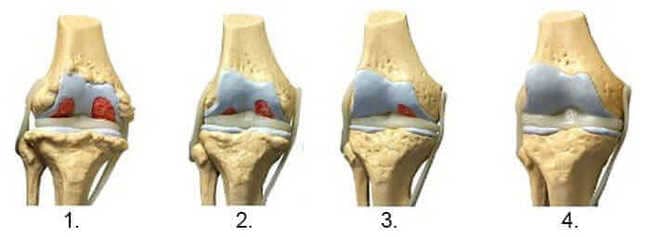

1. Συνέπειες του υποσιτισμού. Πρέπει να χρησιμοποιήσετε το "Steplex".

2. Αναγέννηση του αρθρικού χόνδρου μετά από 2 εβδομάδες εφαρμογής του "Steplex".

3. Αναγέννηση του αρθρικού χόνδρου μετά από 3 εβδομάδες εφαρμογής του "Steplex".

4. Υγιής άρθρωση μετά από θεραπεία Steplex.